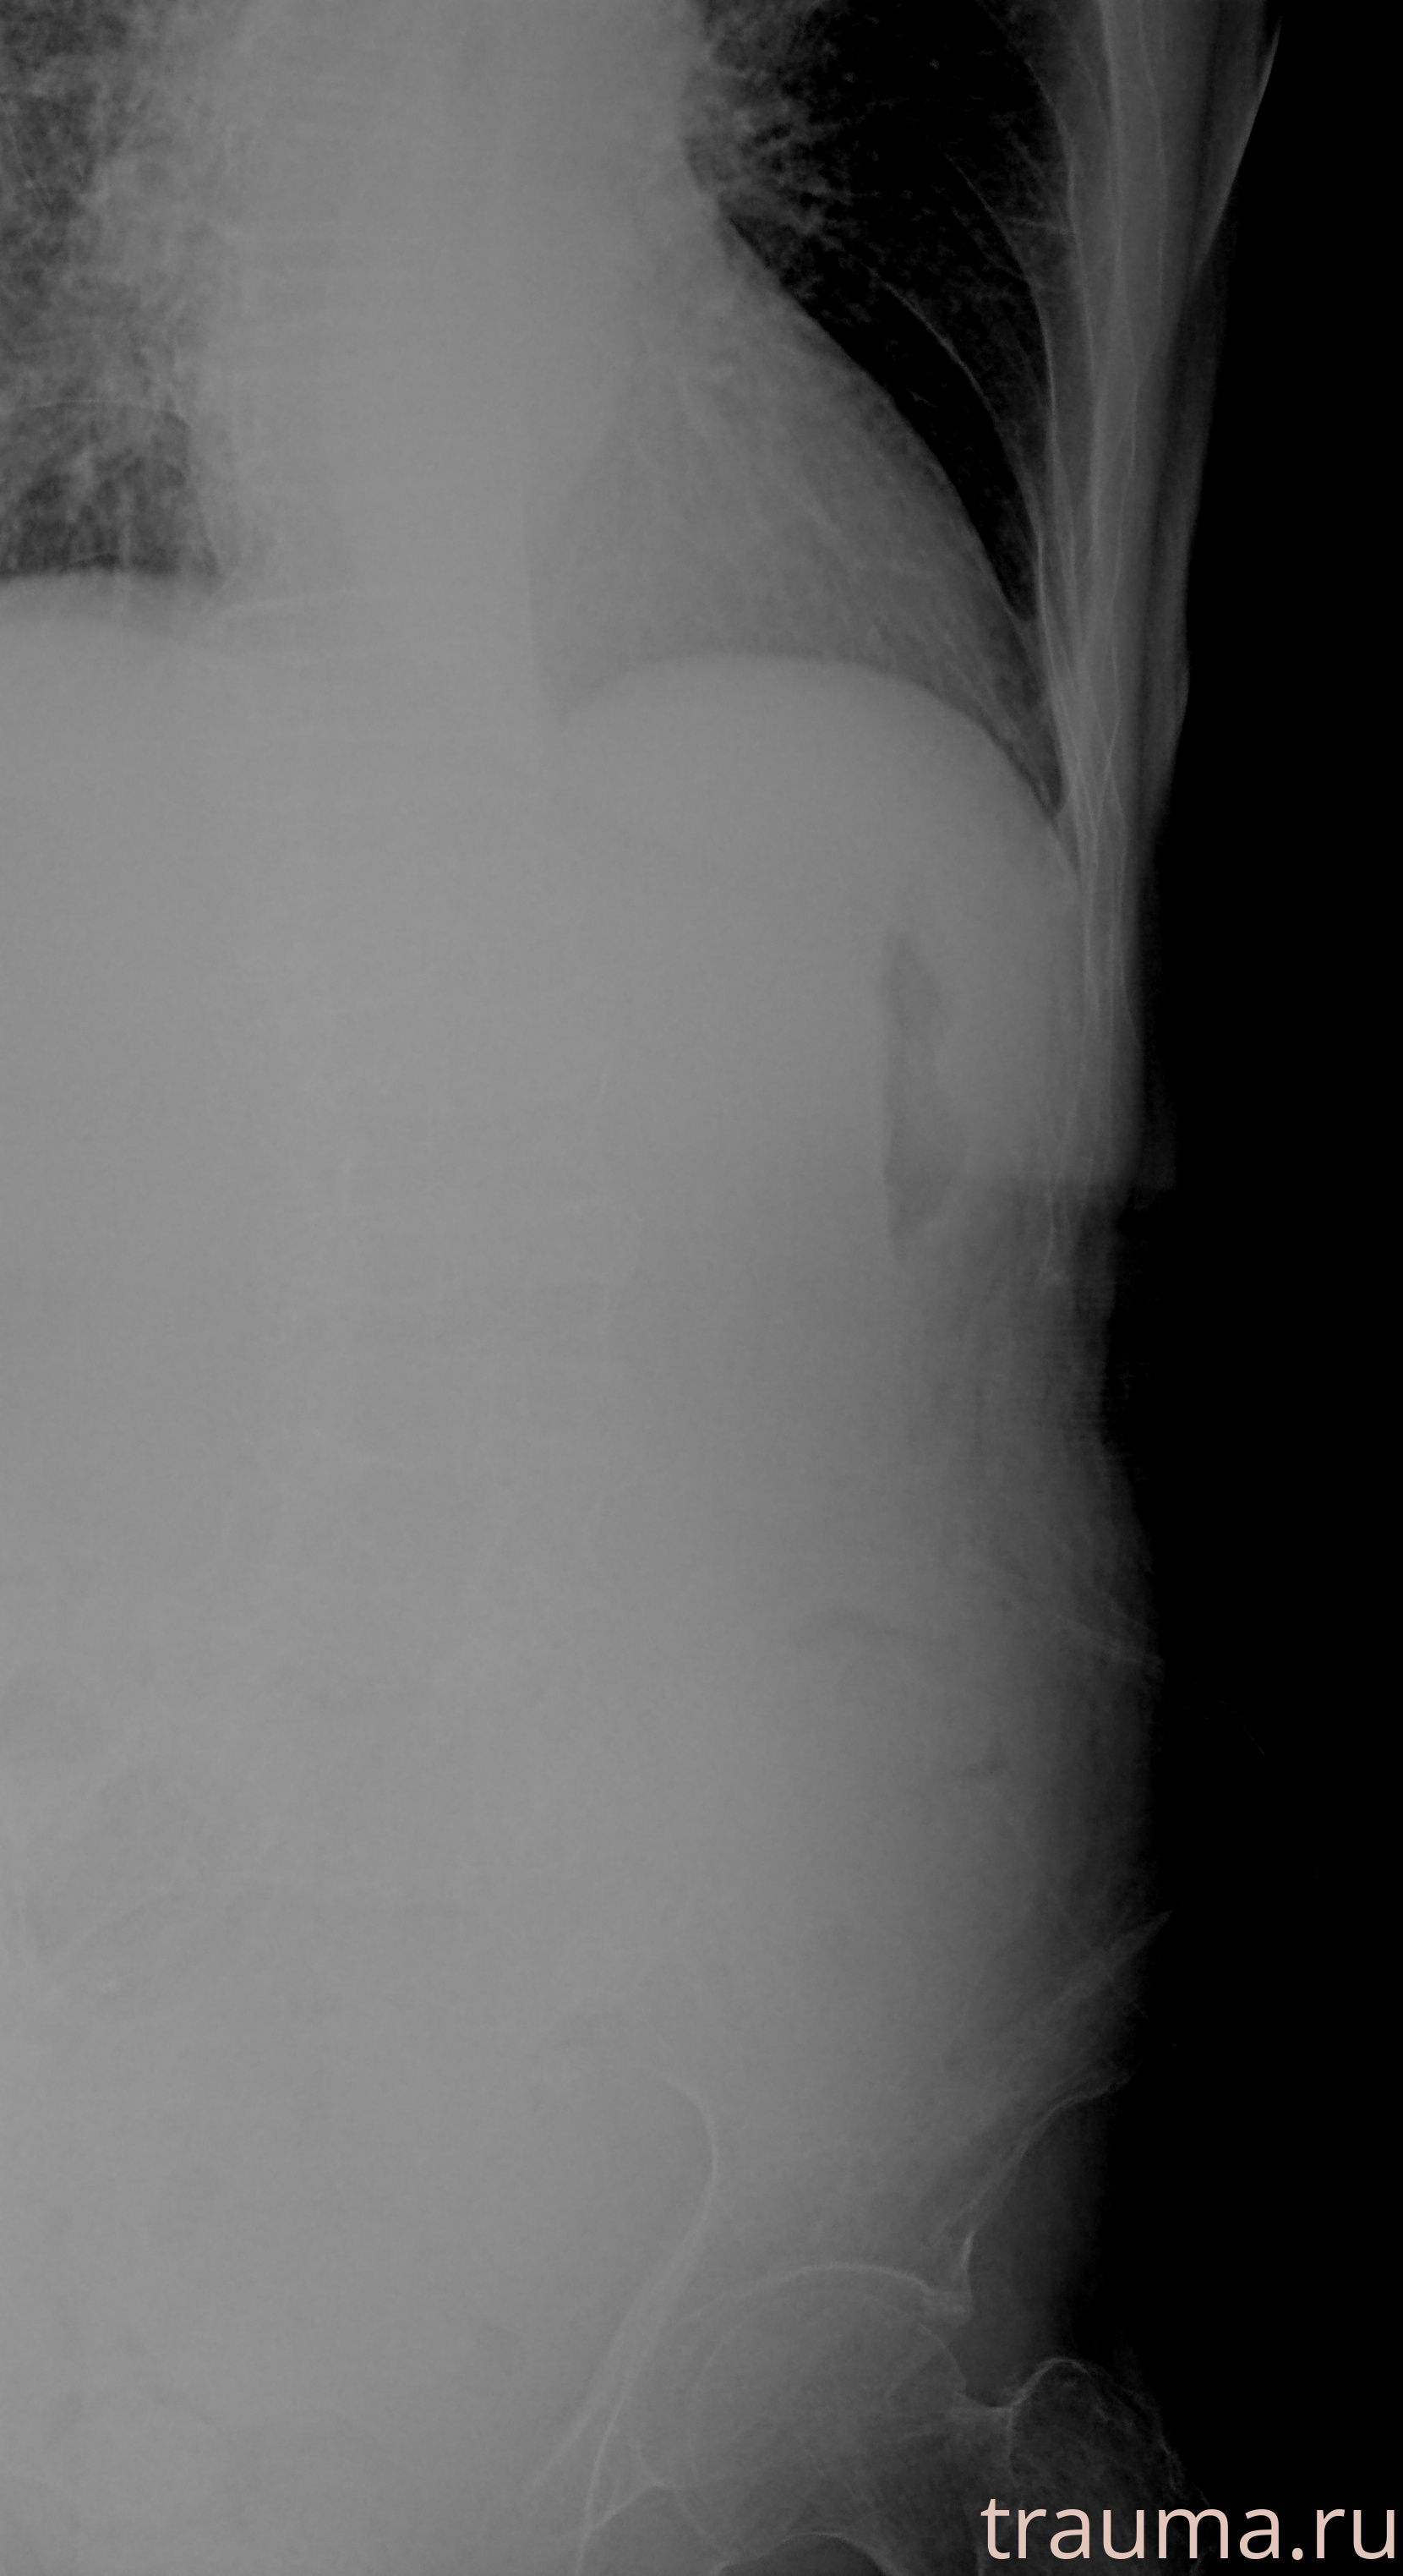

Рентгенограммы

Рентген на дому: по вашему адресу приезжает врач-рентгенолог, травматолог-ортопед с мобильным рентгеновским аппаратом, проводит диагностику травмы или заболевания, делает необходимые рентгенограммы, дает рекомендации по дальнейшему лечению. Получить качественные снимки в домашних условиях возможно благодаря уникальной методике, разработанной МосРентген Центром для института  Склифосовского

при переломе шейки бедра и пневмонии от компании МосРентген Центр - партнера Института имени Склифосовского